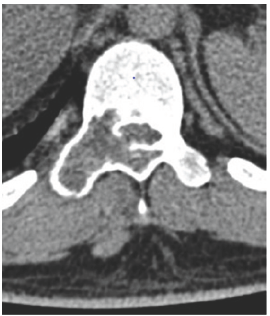

MSCT scan was performed to help in the diagnosis as showen in (Figure 4-7).

Figure 4:

Figure 5:

Figure 6:

Figure 7: